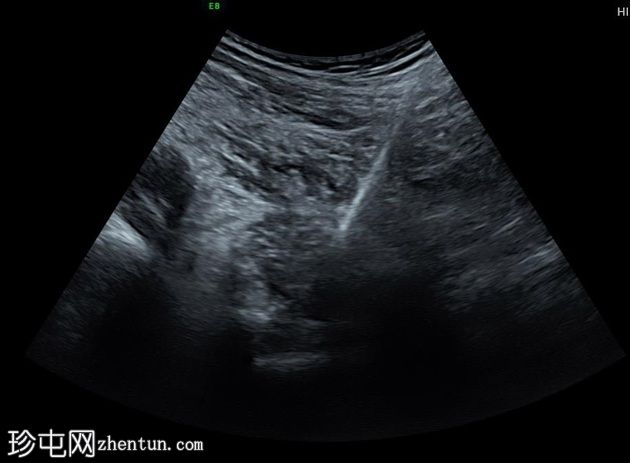

超声

检查

矢状位

在超声引导下,对位于左侧大腿内侧上部的膨胀性溶骨性破坏性肿块进行了穿刺活检。